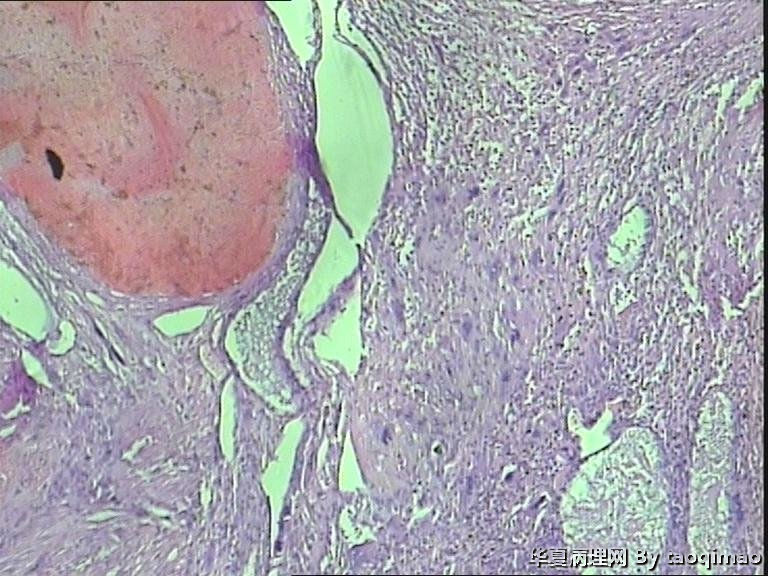

• 功血,滋养细胞浅肌层?图2

图2

上一组图是全子宫切除后宫内膜及浅肌层的切片,取材时发现在子底及后壁有暗紫色血凝块与宫内膜分界不清

追问病史 除外绒癌 侵袭性葡萄胎